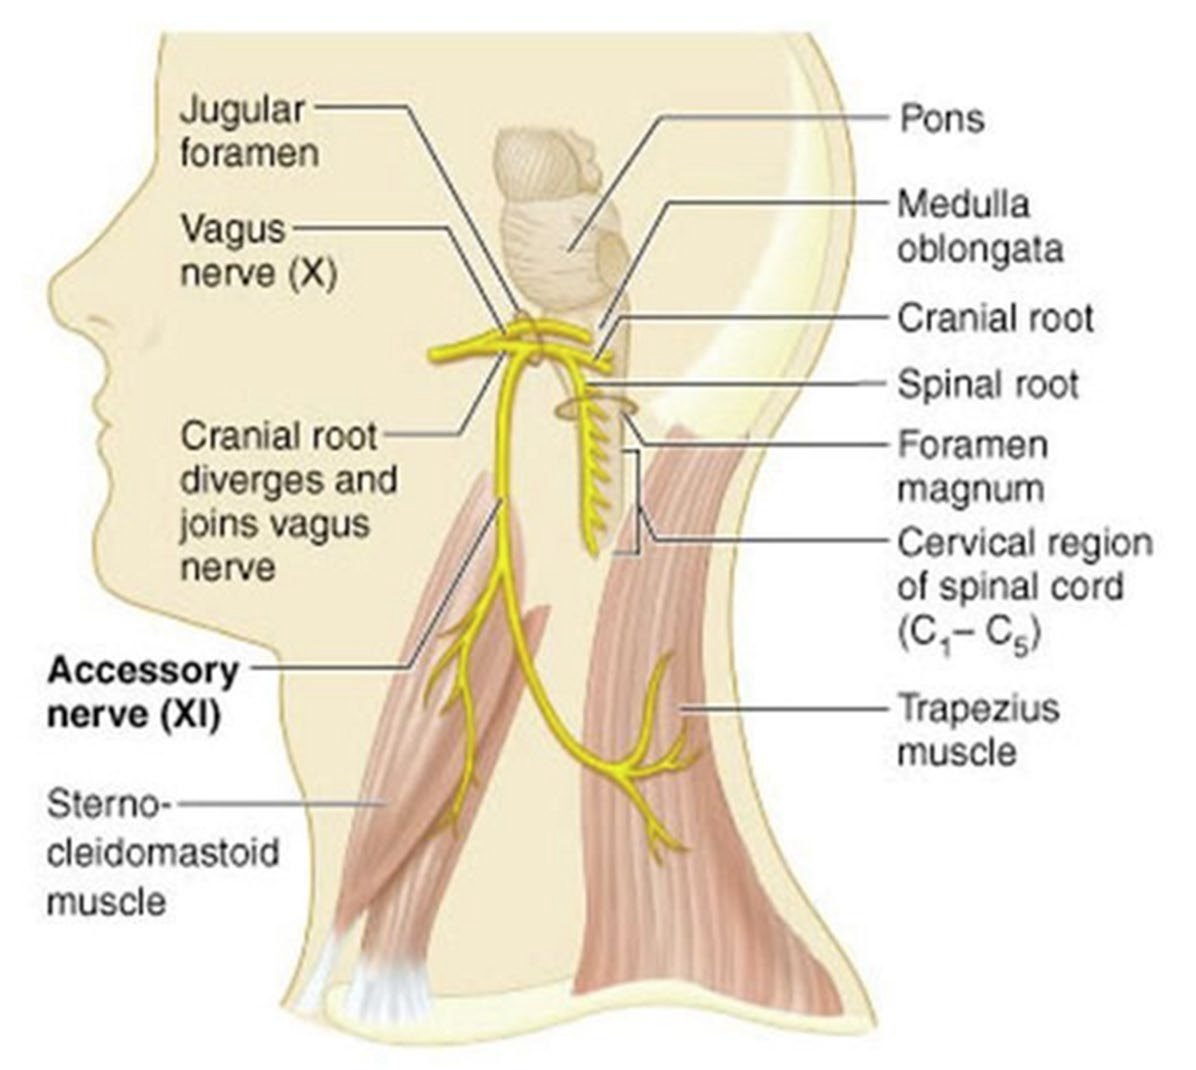

CN XI

- Spinal root(C1-C5)混合

- 向後支配SCM, Trapezius